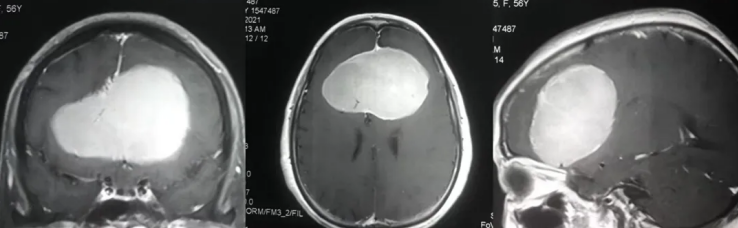

今年60多岁的退休老师王女士在2012年就检查出有“左侧额部大脑镰旁脑膜瘤”,由于肿瘤不到3cm加上无症状,先进行了保守治疗。2018年复查,脑膜瘤已大于5cm,逐渐出现肢体无力,复查MR显示肿瘤侵犯静脉窦、压迫功能区。

国内各大医院求诊,均被告知手术难度大,肿瘤因为靠近大静脉窦难以全切,且肿瘤靠近运动功能区,术后瘫痪可能极大(60-100%不等),而这对于人和一个人和家庭都是惨痛的,除了生活难以自理的经济负担,对于病人和家人也是巨大心理负担。

家人辗转求医最终找到INC德国巴特朗菲教授,王女士的治疗才迎来转机。在教授所在的德国INI国际神经学研究所、由INC德国巴特朗菲教授主刀的一场高质量手术直接全部切除了患者大脑深部复杂部位的脑膜瘤,她大脑中的“定时炸弹”被彻底摘除。如今手术已过去了1年半,从其术前MR、刚手术后的MR、术后1年半多的MR可以清楚看到未见复发迹象,患者现在一切生活如常,幸福的晚年生活不必再被可怕的肿瘤打扰。

术前MR